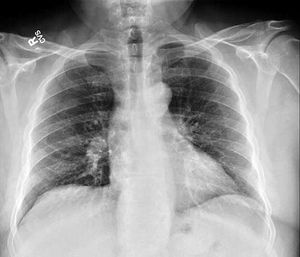

A 59-year-old man with medical history significant for hypertension who presented with an episode of severe coughing, choking and labored breathing which occurred while talking and laughing, raising the suspicion for aspiration. Upon presentation to emergency department, he denied any chest pain, shortness of breath, and coughs. Review of systems was otherwise negative.